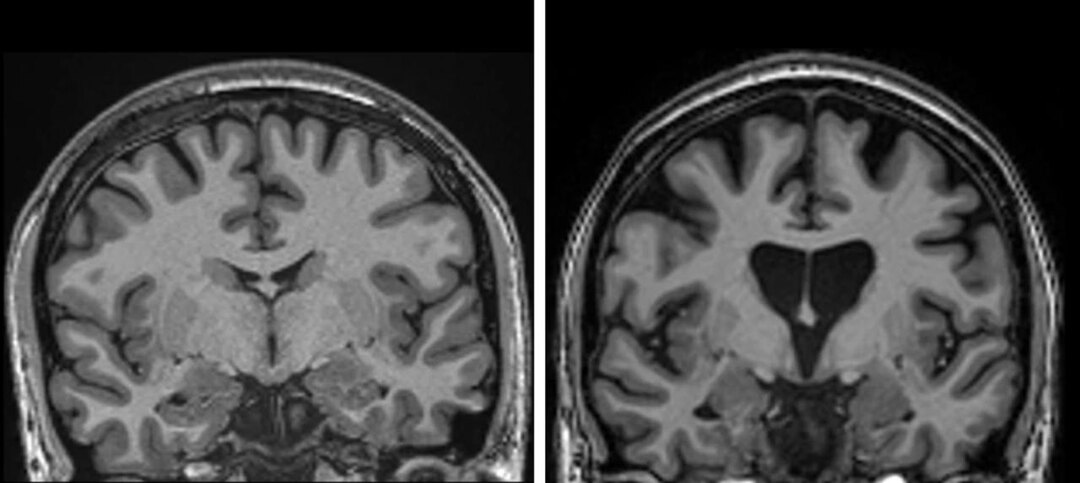

Ученые придумали первое лекарство против болезни Хантингтона, и им оказались… ГМО-вирусы. Это одна из самых страшных болезней мозга: что-то вроде Альцгеймера и Паркинсона, только в одном флаконе. Болезнь генетическая, то есть люди рождаются с ней, и всю их жизнь в мозге копятся дефектные белки. На фотографиях видно, как мозг постепенно умирает: отверстие в центре увеличивается в десятки раз, а число извилин буквально уменьшается. Примерно к 60 годам больной теряет память, не может двигаться, говорить и даже глотать. Никаких лекарств от этой болезни нет, так что пациенты неизбежно умирали. Но недавно ученые опробовали новый препарат — безвредные ГМО-вирусы. Их вводили прямо в мозг через специальную трубку. Этим вирусам полностью перепрошили гены так, чтобы они могли делать всего одну вещь — производить лекарство прямо в мозге пациента, то есть в эпицентре болезни. Вирусы проживут там десятки лет, и все это время будут бороться с болезнью Хантингтона изнутри. То есть лекарство вкололи вс